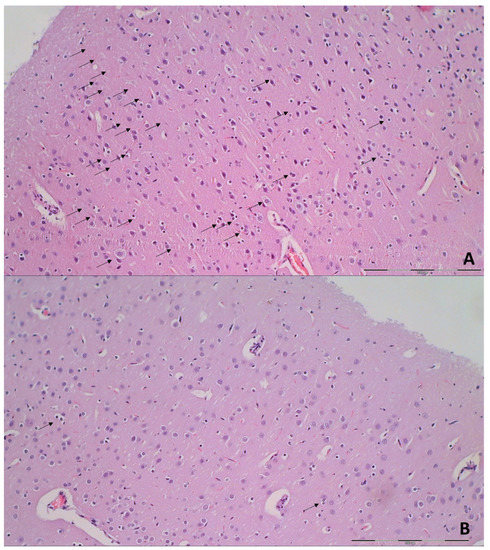

3.9. Histology

| Brain Area | Grading | Percent Area Affected | Morphological Changes |

|---|---|---|---|

| Cerebral and cerebellar cortex, hypothalamus, thalamus, hippocampus | 1 | ≤10 | Small, patchy, complete or incomplete infarcts |

| 2 | 20–30 | Partly confluent complete or incomplete infarcts | |

| 3 | 40–60 | Large confluent compete infarcts | |

| 4 | >75 | In cortex; total disintegration of the tissue, in hypothalamus, thalamus, hippocampus; large complete infarcts | |

| Cerebral and cerebellar cortex, hypothalamus, thalamus, hippocampus | 1 | ≤20 | A few karyopyknotic of neuronal cells |

| 2 | 50 | Patchy areas of karyopyknotic areas | |

| 3 | 75 | More extensive of karyopyknotic areas | |

| 4 | 100 | Complete infarction |